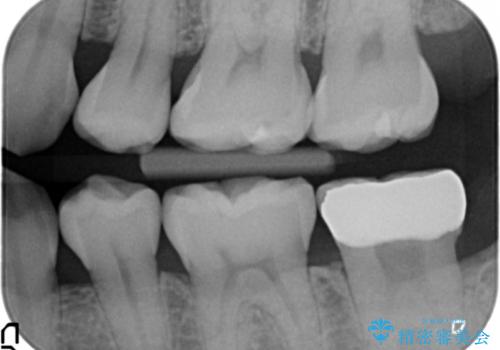

- 26万円(左下7:ジルコニアクラウン 10万円、仮歯 1万円、歯周外科手術(APF) 10万円、静脈内鎮静法 5万円)費用は治療当時の料金となります

他院で難しいと言われた虫歯治療をきっちりすることができて、とても喜んでいただきました。